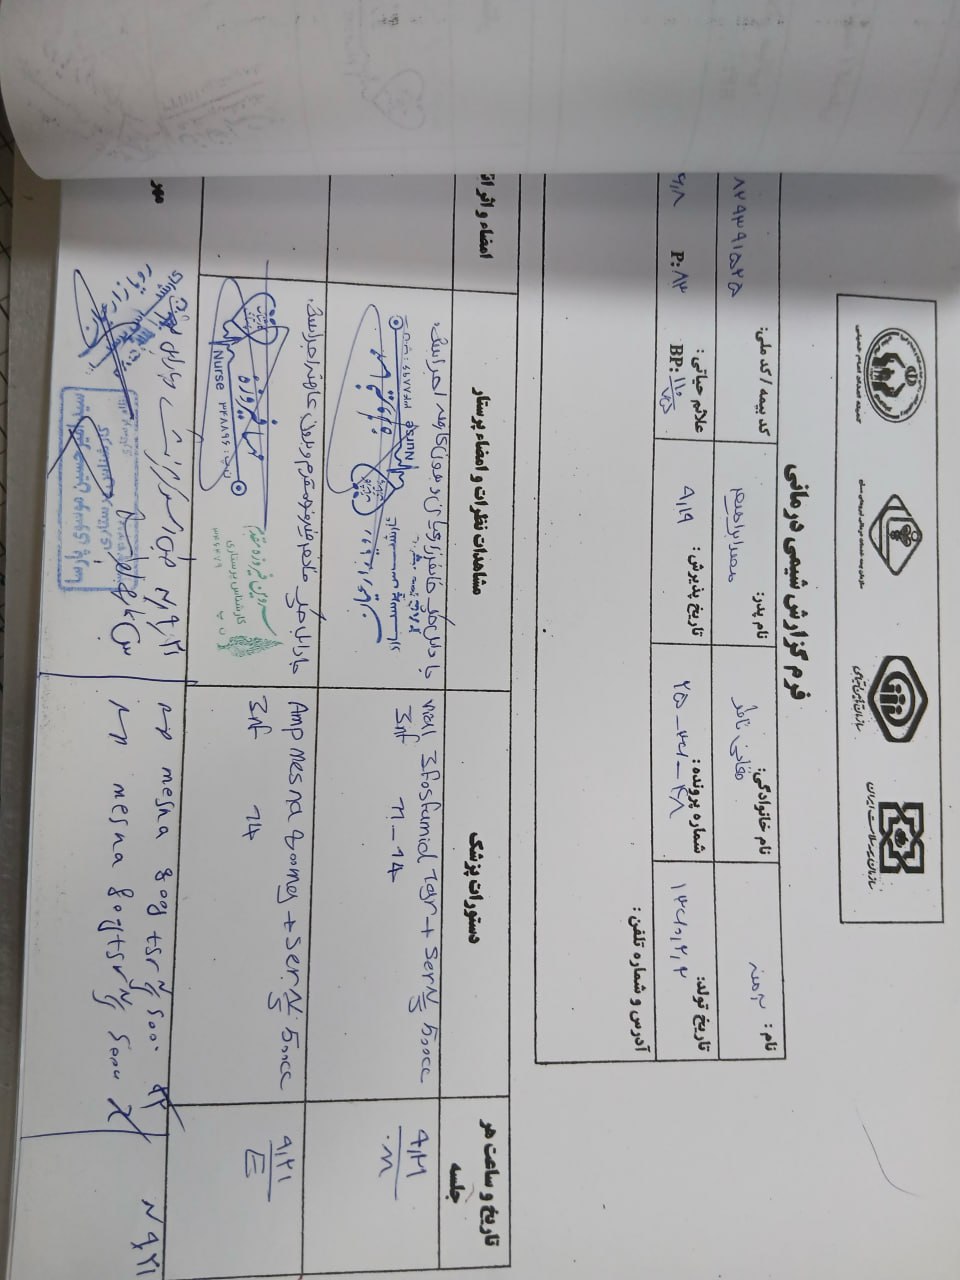

به ترتیب؛ روز ها: ۱۹ آبان, ۲۸ آذر, ۲۹ آذر, ۳۰ آذر

به ترتیب؛ روز ها: ۱۹ آبان, ۲۸ آذر, ۲۹ آذر, ۳۰ آذر

به ترتیب؛ روز ها: ۲۸ آذر, ۲۹ آذر, ۳۰ آذر, ۱ دی

۱ دی